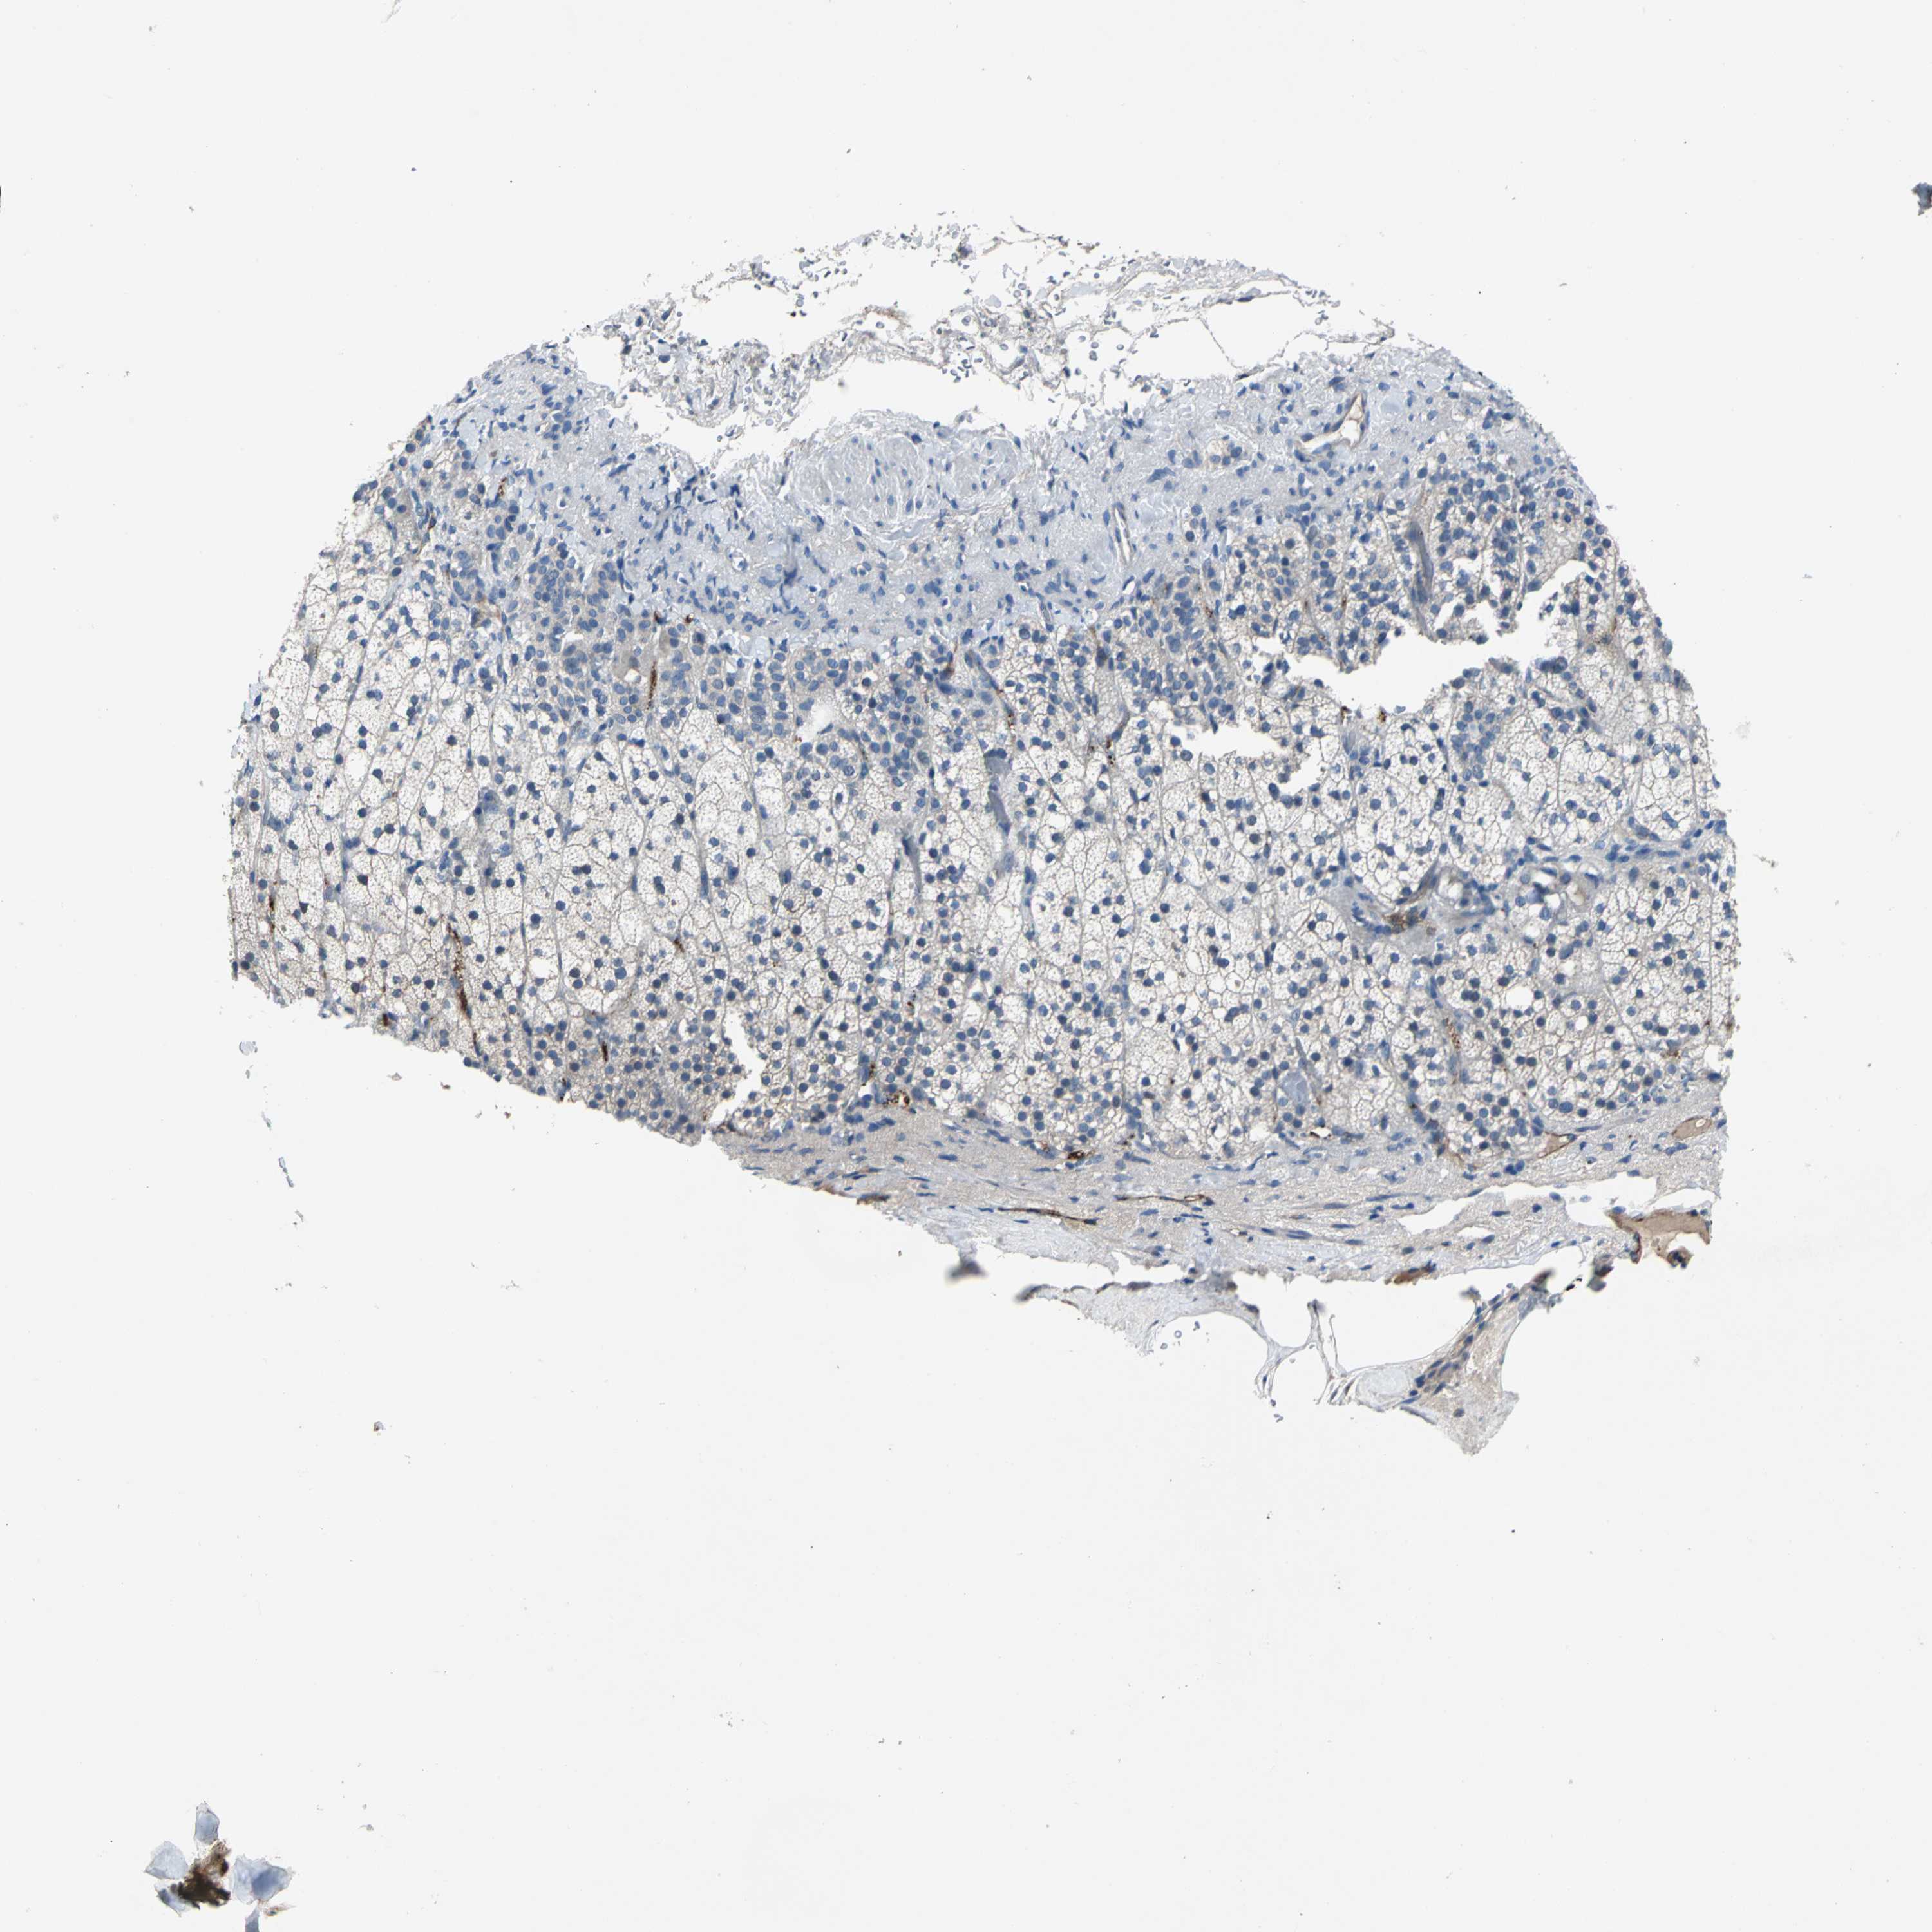

ADRENAL GLAND - Antibody stainingi

Antibody staining in the annotated cell types in the current human tissue is reported as not detected, low, medium, or high, based on conventional immunohistochemistry profiling in selected tissues. This score is based on the combination of the staining intensity and fraction of stained cells.

Each image is clickable and will lead to virtual microscopy that enables deeper exploration of all samples and also displays staining intensity scores, fraction scores and subcellular localization as well as patient and tissue information for each sample.

Antibody HPA002655Antibody HPA005990Antibody CAB002145

Glandular cells LowNot detectedNot detected